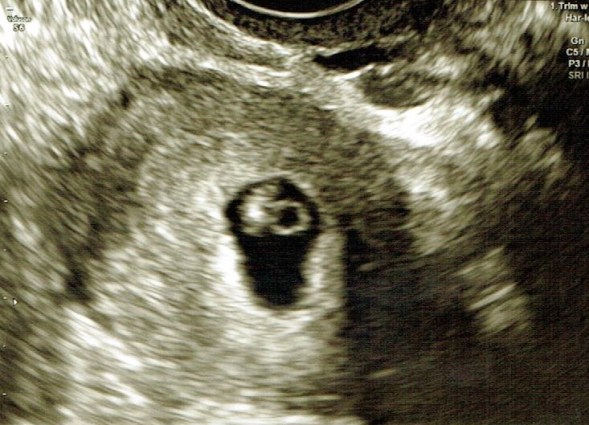

Today marked 8 weeks. It is still relatively unbelievable that I have a baby growing inside me. No matter how many times I look at the ultrasound pictures, it still doesn’t quite seem real. For someone who has experienced infertility and an early loss before, this is a relatively common way to feel. While others may be celebrating, or looking at baby things, all I can think about is the statistics, like the one shared above.

Apparently today baby says “hello”. He or she measured at 7 weeks, 2 days, but decided to be scrunchy during the ultrasound, so could actually be a bit bigger. His or her heart was beating at 168 bpm, which is excellent.